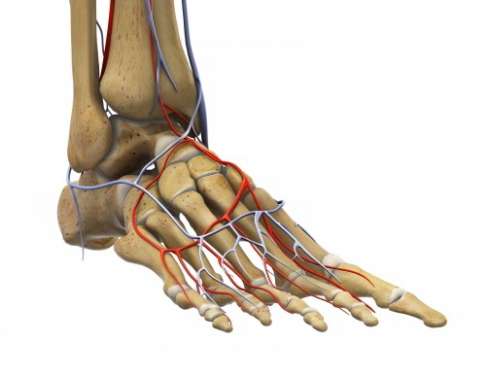

Schmerzen im Mittelfuß (Metatarsalgie): Nervenkompressionssyndrome

Ansicht des Fußes von der Fußsohle aus: Zahlreiche Nerven tragen zur Sensibilität und Geschicklichkeit des Fußes bei. Werden diese Nerven eingeklemmt, entstehen neurogene (nervenbedingte) Fußschmerzen. Dazu zählen das Morton Neurom, das Tarsaltunnelsyndrom und die Kompression des Baxter-Nervs an der Ferse. © Viewmedica

Am Fuß verlaufen zahlreiche Nerven, die dieses wichtige Bewegungsorgan mit Gefühls- und Steuerungssignalen für Muskelaktivität und Gleichgewicht versorgen. Nerveneinklemmungen oder -verletzungen verursachen ein weites Spektrum an Missempfindungen (Parästhesien). Die Fußschmerzen können von dumpfen Schmerzen und Taubheitsgefühl bis zu brennenden, scharfen Schmerzen reichen, die jeden Schritt zur Qual machen.